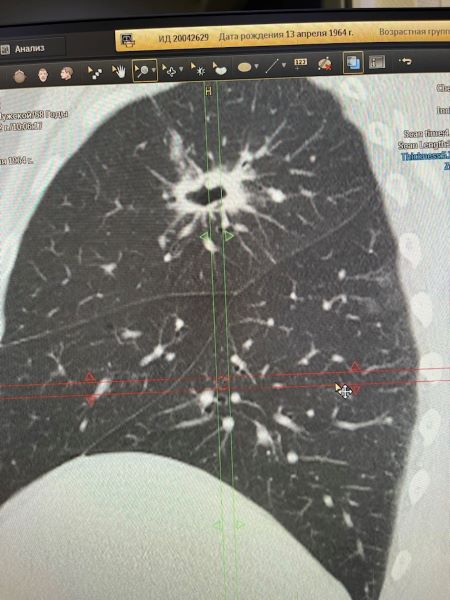

Врачом-рентгенологом, КТ-диагностом Якушевой И.А. пациенту было проведено исследование органов грудной клетки, нативным методом (без контрастирования), на МСКТ фирмы Филипс, после которого на многочисленных, тонкосрезовых томограммах, справа в верхней доле выявлена дополнительная тень в виде зоны консолидации с просветлением в центре, формирующейся полости, с отточной дорожкой к корню лёгких. Других видимых изменений не определялось.

По Cito ( в течении часа) были выполнены описание и расшифровка, с записью на цифровой носитель. По итогам исследования поставлено заключение: «Инфильтративный туберкулёз с распадом».